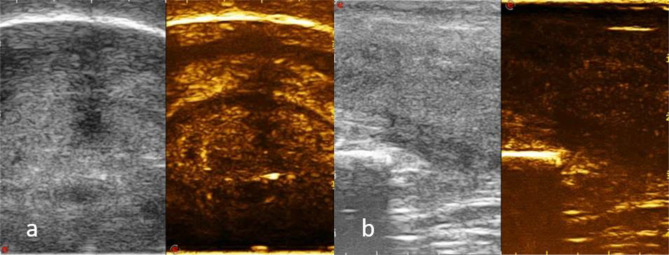

Fig. 4.

a, b CEUS shows a large abscess located in the ventral side of the middle and distal part of the cavernous body (arrowhead) and extended up to the distal dorsal side of the cavernous body (arrowhead) with the interruption of the albuginea tunic (arrow)